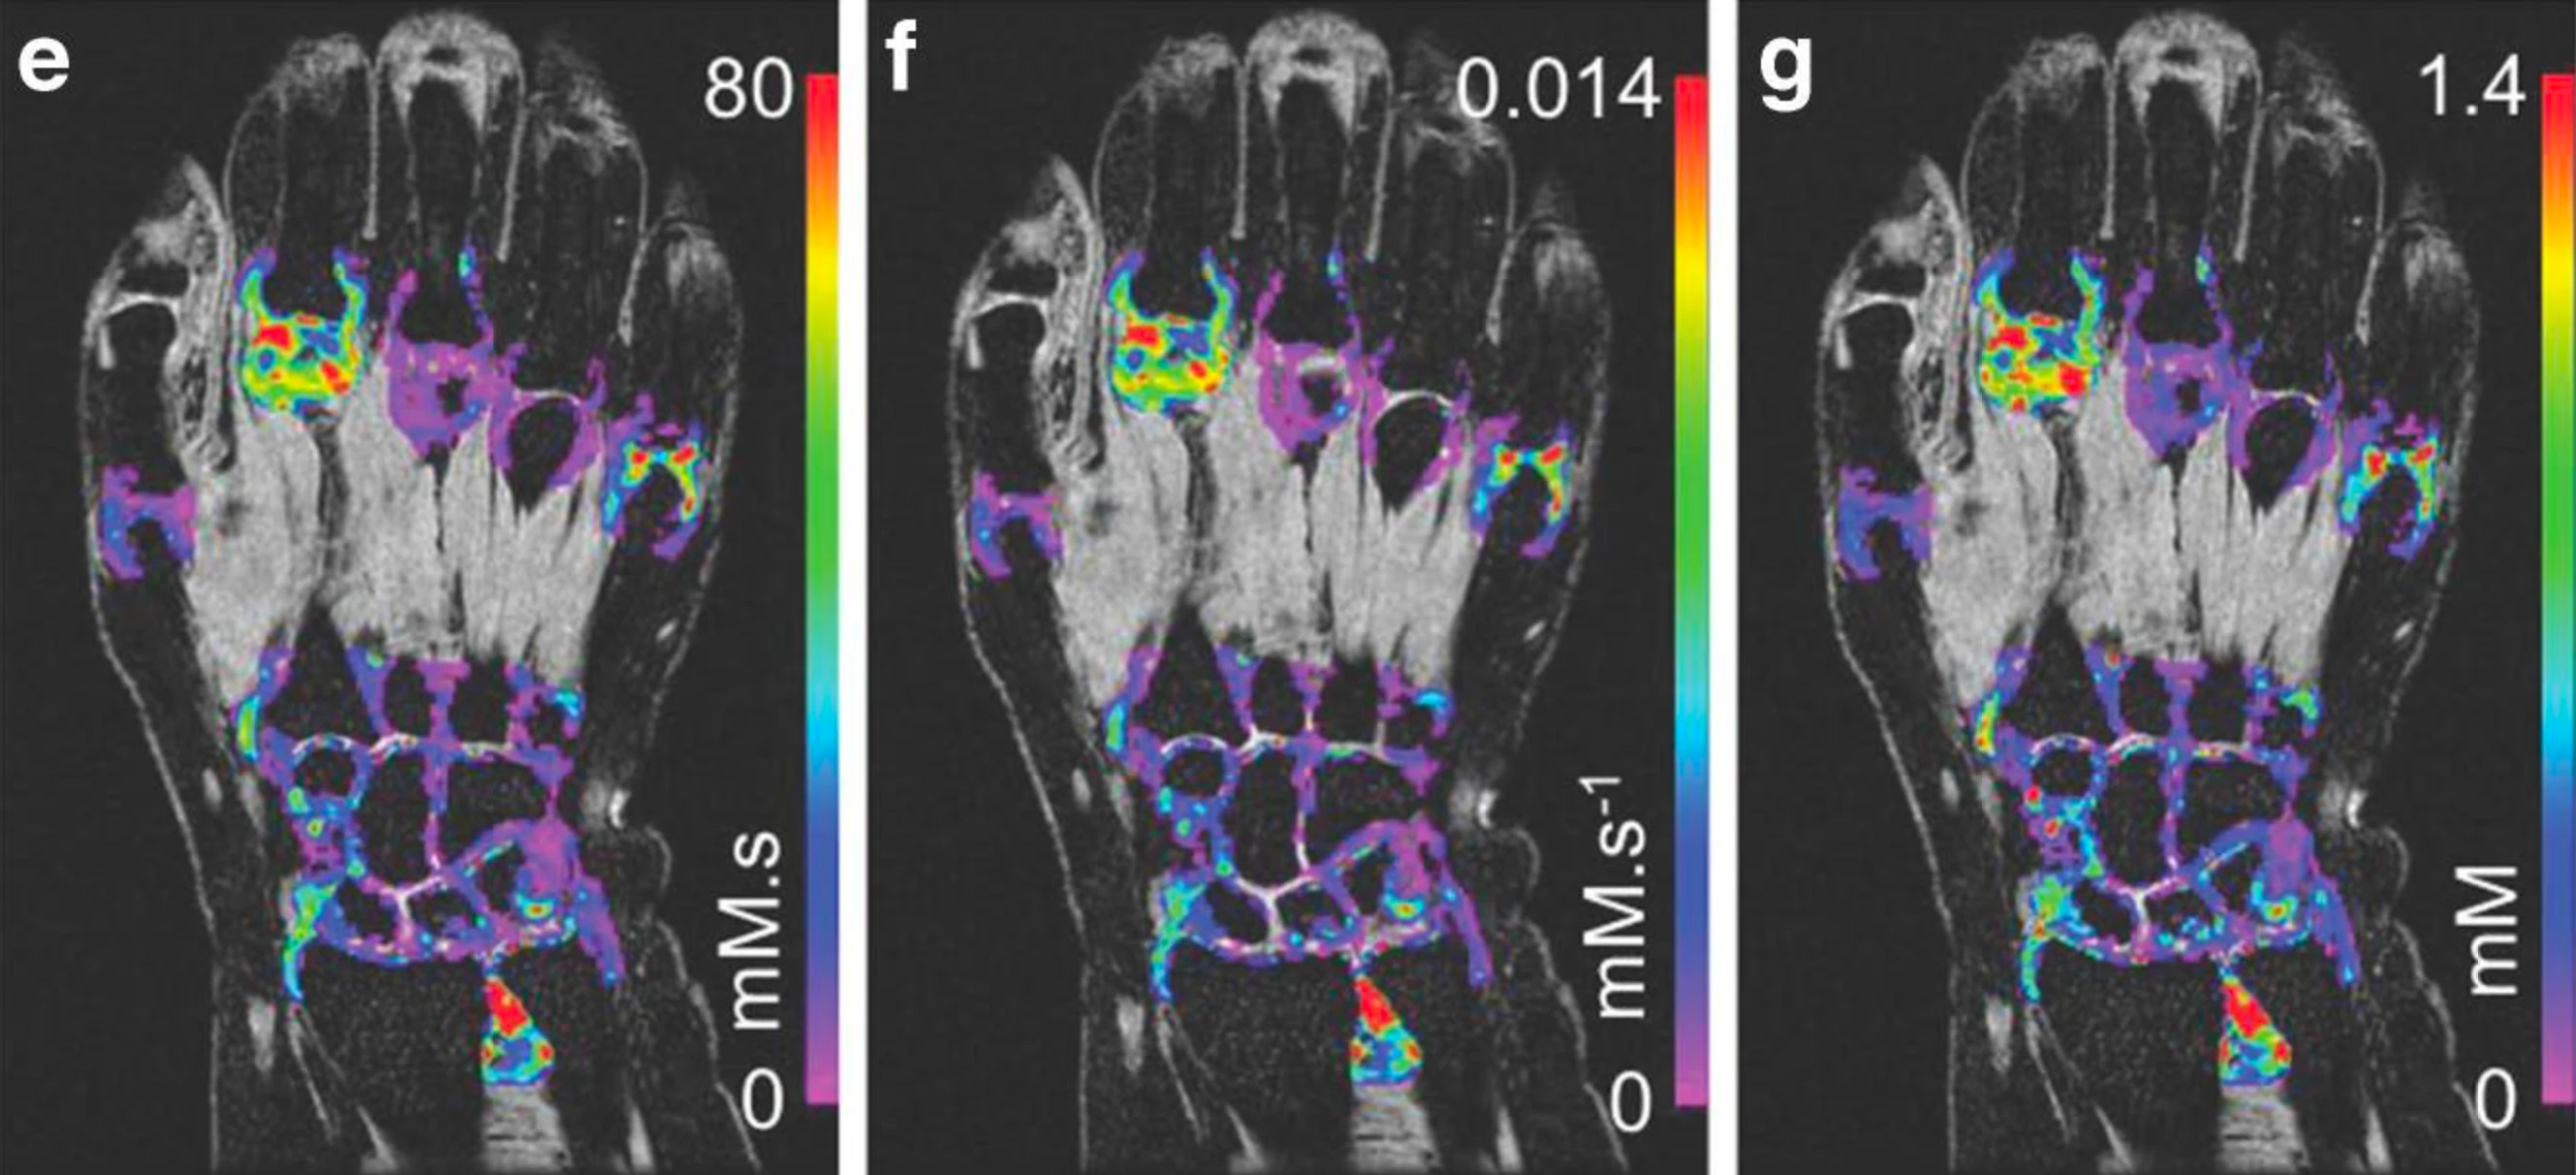

From study design to final reporting, Bioxydyn delivers repeatable MRI biomarkers that reveal tissue function, physiology and change. Our operational excellence and metrology help you compare results across sites, scanners and timepoints.

VoxelFlow supports your clinical trial end-to-end, delivering reliable, repeatable and auditable outputs. It is compliant with FDA 21 CFR Part 11

Disease areas and services supporting quantitative MRI biomarkers across clinical trials.